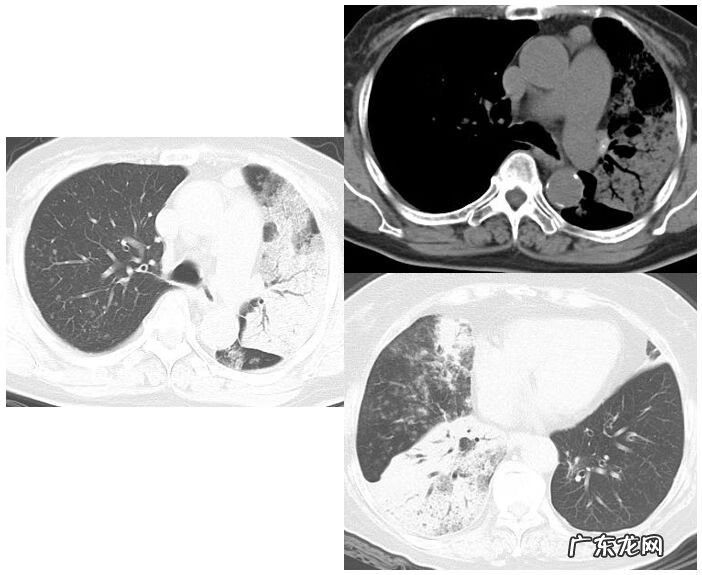

这是一位36岁的女性,咳嗽3个月,咳白色粘痰 。我们来看这个双肺下叶弥漫磨玻璃影,里边有细支气管壁增厚、牵拉、稍扩张,在胸膜下(图9) 。这是SLE继发OP,患者使用激素治疗3月,肺内病变基本吸收仅残留少许磨玻璃密度影 。

图9